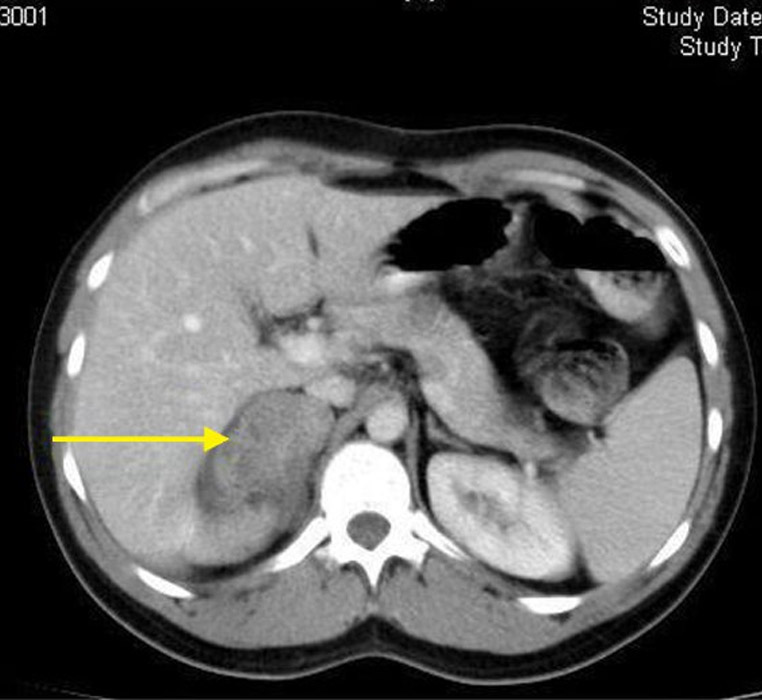

Nefrectomía Parcial Laparoscópica

Esta comprobado que la cirugia conservadora del riñon (ahorradora de nefronas), mejora la sobrevida global de los pacientes sometidos a tratamiento del cancer de riñon, disminuyendo las tasas de insuficiencia renal cronica y eventos cardiovasculares entre otros.